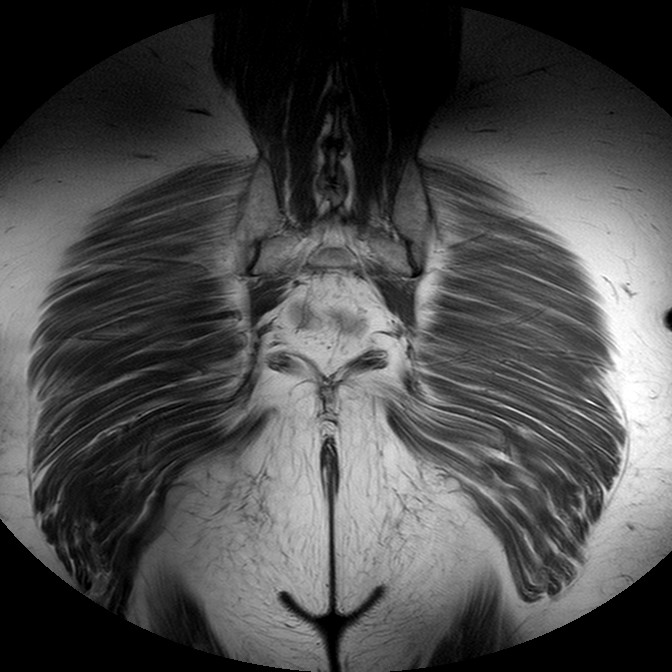

Esami: RMN BACINO

T1w TSE

Evidenti e simmetriche alterazioni osteofitosiche in regione coxo femorale con riduzione delle rime articolari. Degenerazione completa del cercine glenoideo. Non attuali segni di versamento articolare. Non segni di edema osseo che escludono attuale algodistrofia od osteonecrosi. Lieve e simmetrica riduzione del trofismo della muscolatura glutea.